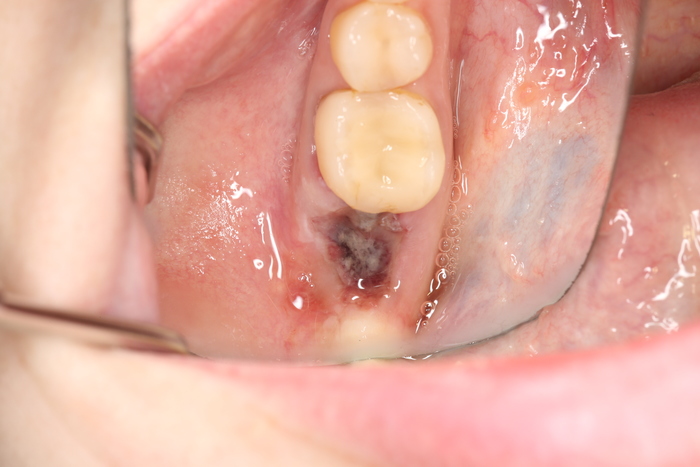

Далее проведена пластика десны, снова два месяца ожиданий и установка временной коронки:

Ну, такое, согласен, но это начало.

Еще через пару месяцев временную коронку сняли для изготовления новой:

И вот картинка спустя полгода «ношения» новой временной коронки: